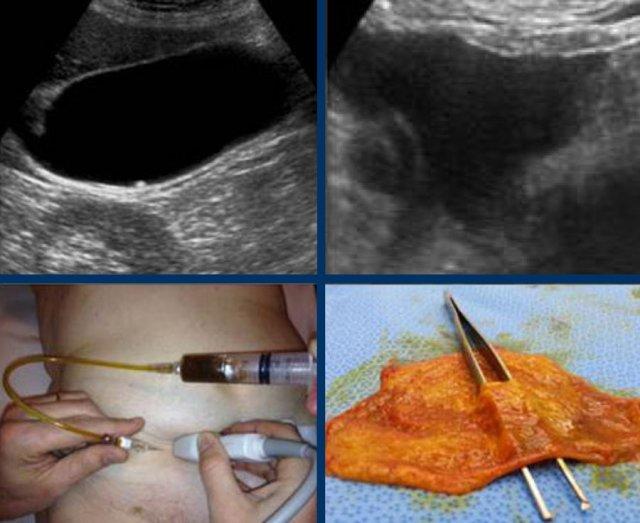

Hình ảnh của một bệnh nhân bị phình to túi mật cấp tính do sỏi kẹt.

Sỏi kẹt không thể hiển thị được trên trục dọc của túi mật, do vị trí nằm ở phía trong của ống túi mật (mũi tên).

Hình ảnh của một phụ nữ trẻ bị cơn đau quặn mật kéo dài 8 giờ.

Siêu âm cho thấy sỏi bị kẹt và phù nề túi mật.

Bệnh nhân đi bộ trong một giờ và siêu âm được thực hiện lại.

Sỏi đã bong ra, và phù nề tái tưới máu xuất hiện như những dấu hiệu chứng nhân thầm lặng của cơn đau quặn.

CRP vẫn bình thường.

Khi phù nề túi mật đã biến mất, bệnh nhân không còn đau quặn nữa.

Tuy nhiên bệnh nhân thường có cảm giác “đau âm ỉ” mơ hồ ở vùng thượng vị như thể ai đó đã “đấm vào bụng họ”.